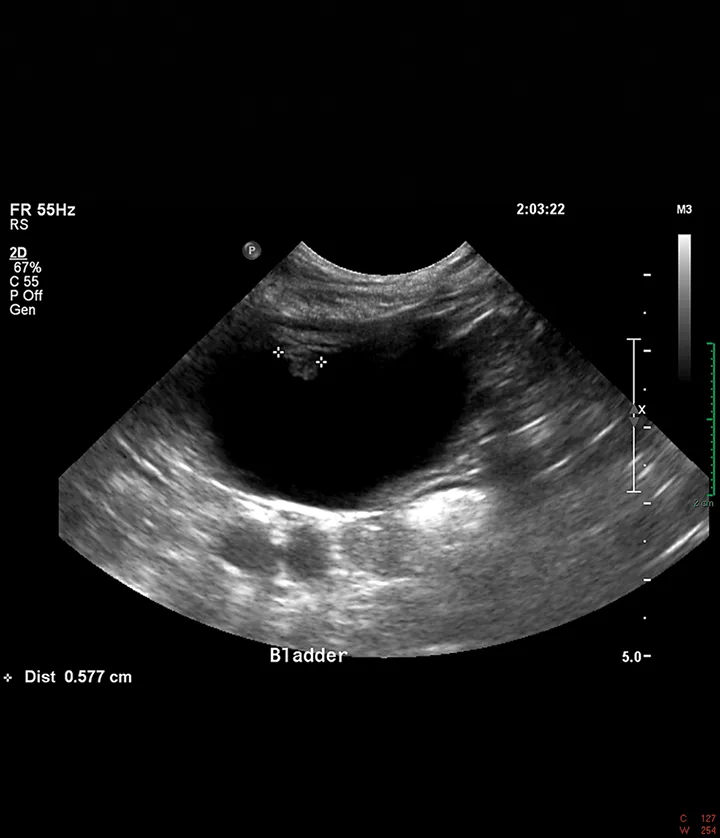

Abdominal ultrasound showed a mildly thickened cranioventral urinary bladder wall with a 6-mm irregular, polypoid, inhomogeneous mass extending into the lumen (Figure 1). No other abnormalities were identified in the abdomen. Cystoscopy revealed an irregular mass on the cranioventral wall with an area of ulceration and a fibrous tag protruding into the lumen (Figure 2). The remainder of the bladder appeared friable. Aerobic and Mycoplasma spp cultures of the bladder wall were negative. Histopathologic examination of biopsies showed mild lymphocytic cystitis.

FIGURE 2

Cystoscopic image of an ulcerated polypoid mass extending into the bladder lumen